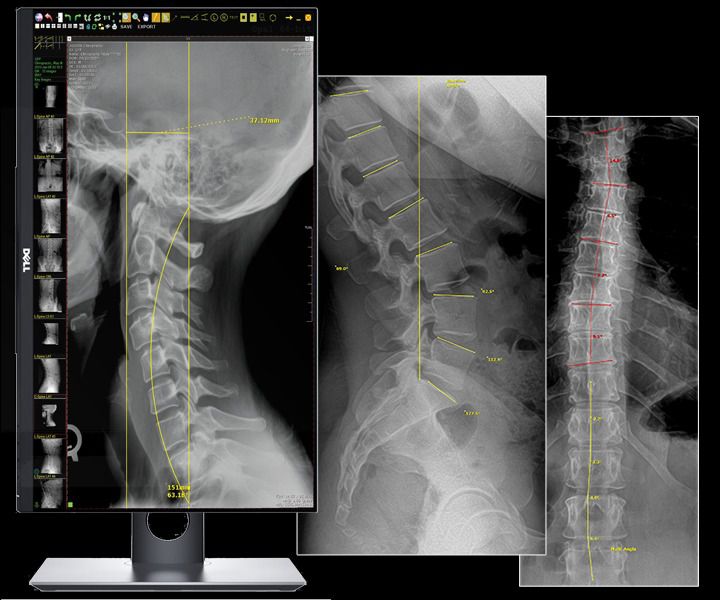

20/20 Plaque DR avec poste d'acquisition

CARACTÉRISTIQUES HYBRIDES : 3 configurations de fonctionnement uniques